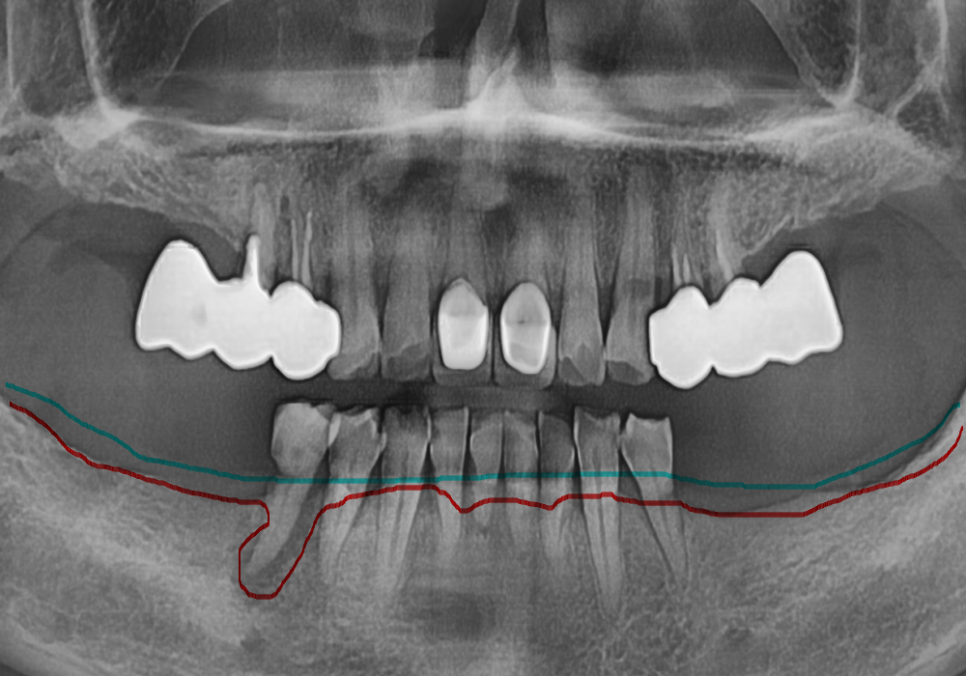

이 환자분은 아래 앞니가 흔들려

저희 병원에 내원하셨습니다.

방사선 진단 결과,

치조골(뼈)이 전반적으로

많이 흡수되어 있었고,

그로 인해 치아 뿌리를

지지하는 힘이 부족해

치아가 흔들리는 상태였습니다.

또한 뼈가 지지해 주는

치근(뿌리) 길이도 매우 짧아

자연치로 유지하기에는

예후가 좋지 않은 상황으로

판단되었습니다.

그래서 환자분과 충분히 상담 후

발치 후 임플란트 치료로 계획을 세웠습니다.